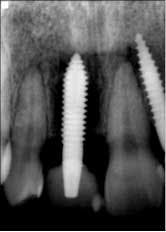

Fig. 6: Postoperative six weeks later.The patient returned for a follow-up eight months later (Fig. 7) and claimed she was careful not to bite into anything with her front teeth and wanted to know if they could be restored with permanent crowns. Impressions were taken and sent to the lab for fabrication of implant crowns. One year post-insertion, the final crowns and radiographs were taken (Figs. 8 and 8a).

Fig. 8a: One year post-insertion — final radiographs.